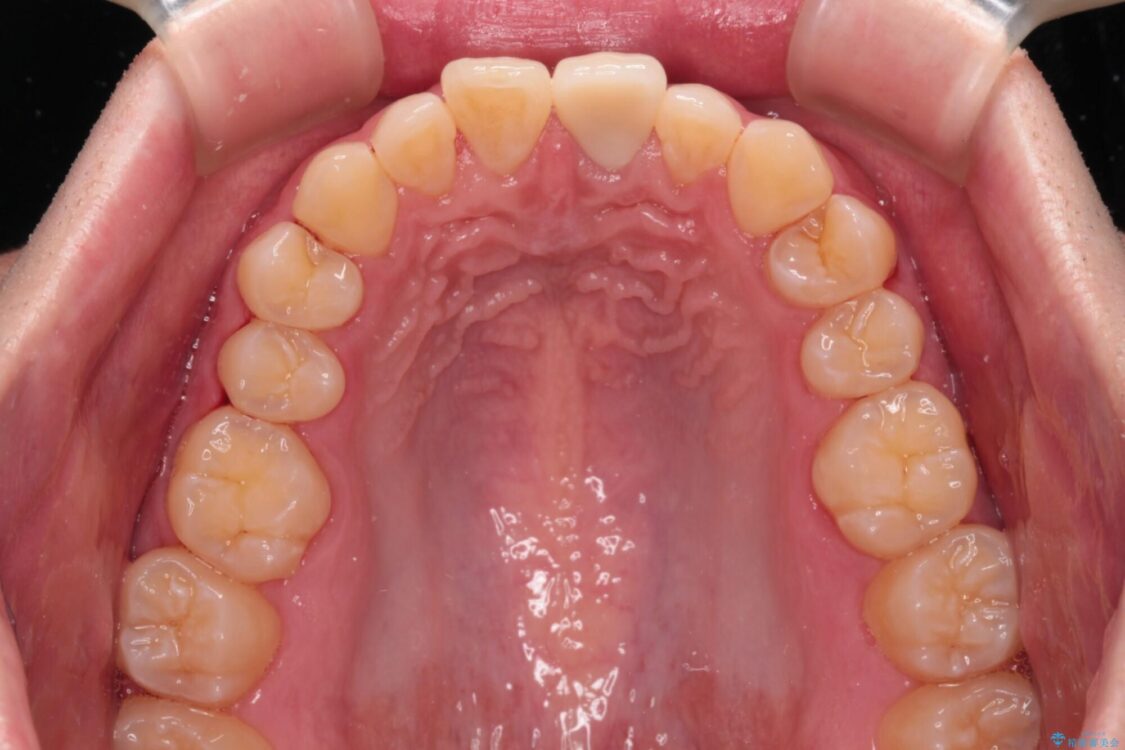

神経を取り除いたことで変色した前歯を気にして来院された患者様です。

根管治療はやり直さずに、ファイバーポストを使用した土台を植立してオールセラミッククラウンにて補綴することとしました。

治療前

• 変色した前歯をオールセラミッククラウンに 治療前画像